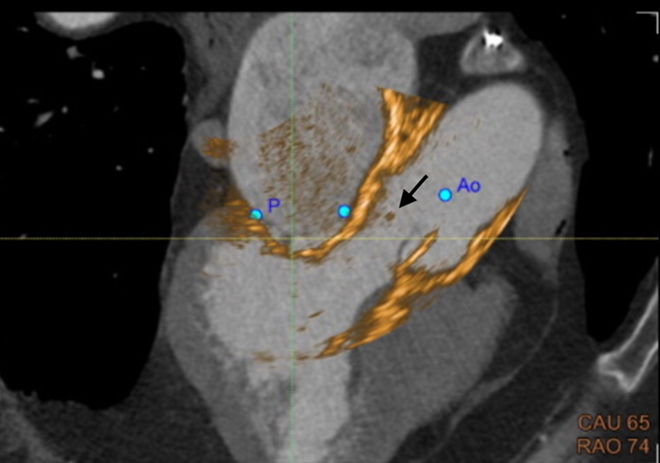

On the current presentation, the patient underwent repeat transthoracic echocardiography with bubble study and contrast-enhanced transthoracic echocardiography, neither of which demonstrated an intracardiac shunt or left ventricular thrombus. Electrocardiographically (ECG) synchronized cardiac computed tomography angiography (cCTA) was then performed as the final diagnostic test, supported by recent evidence demonstrating a higher diagnostic yield than echocardiography in the evaluation of acute stroke (Rinkel et al., 2022). cCTA revealed a 2-mm low-density tissue excrescence arising from the noncoronary cusp of the aortic valve (Figure 1) and simultaneously confirmed the absence of intracardiac thrombus or patent foramen ovale. Guided by cCTA localization, a repeat TEE with three-dimensional (3D) multiplanar reconstruction (Figure 2) successfully visualized the lesion. Intraoperative four-dimensional (4D) TEE with CT fusion—an innovative multimodality integration not previously described for this indication—was subsequently used for precise leaflet localization (Figures 3 and 4). Surgical pathology (Figure 5) demonstrated fibrocalcific degenerative changes of the noncoronary cusp and a small papillary fibroelastoma (PFE), which was deemed the most likely source of the patient’s recurrent cerebrovascular events.

Figure-4

Papillary fibroelastomas, although histologically benign, remain an important and often underrecognized cause of cardioembolic stroke, particularly when small, mobile, and located on left-sided valves. In this case, standard diagnostic evaluation failed to identify an embolic source. Electrocardiographically synchronized cardiac CTA ultimately revealed a subtle 2-mm excrescence on the noncoronary cusp of the aortic valve, which was subsequently confirmed via targeted three-dimensional multiplanar TEE and intraoperative four-dimensional (4D) TEE with CT fusion. Surgical excision demonstrated papillary fibroelastoma on pathology, and the patient has remained stroke-free on follow-up.

Combining CTA with intraoperative 4D TEE overcame these challenges, allowing accurate localization of the lesion, exclusion of other embolic sources, and seamless guidance during surgical resection. Although multimodality fusion imaging has traditionally been used for structural heart interventions such as valve repair and left atrial appendage occlusion (Fortuni et al., 2020), this case demonstrates its potential usefulness in the evaluation of embolic stroke of undetermined source.